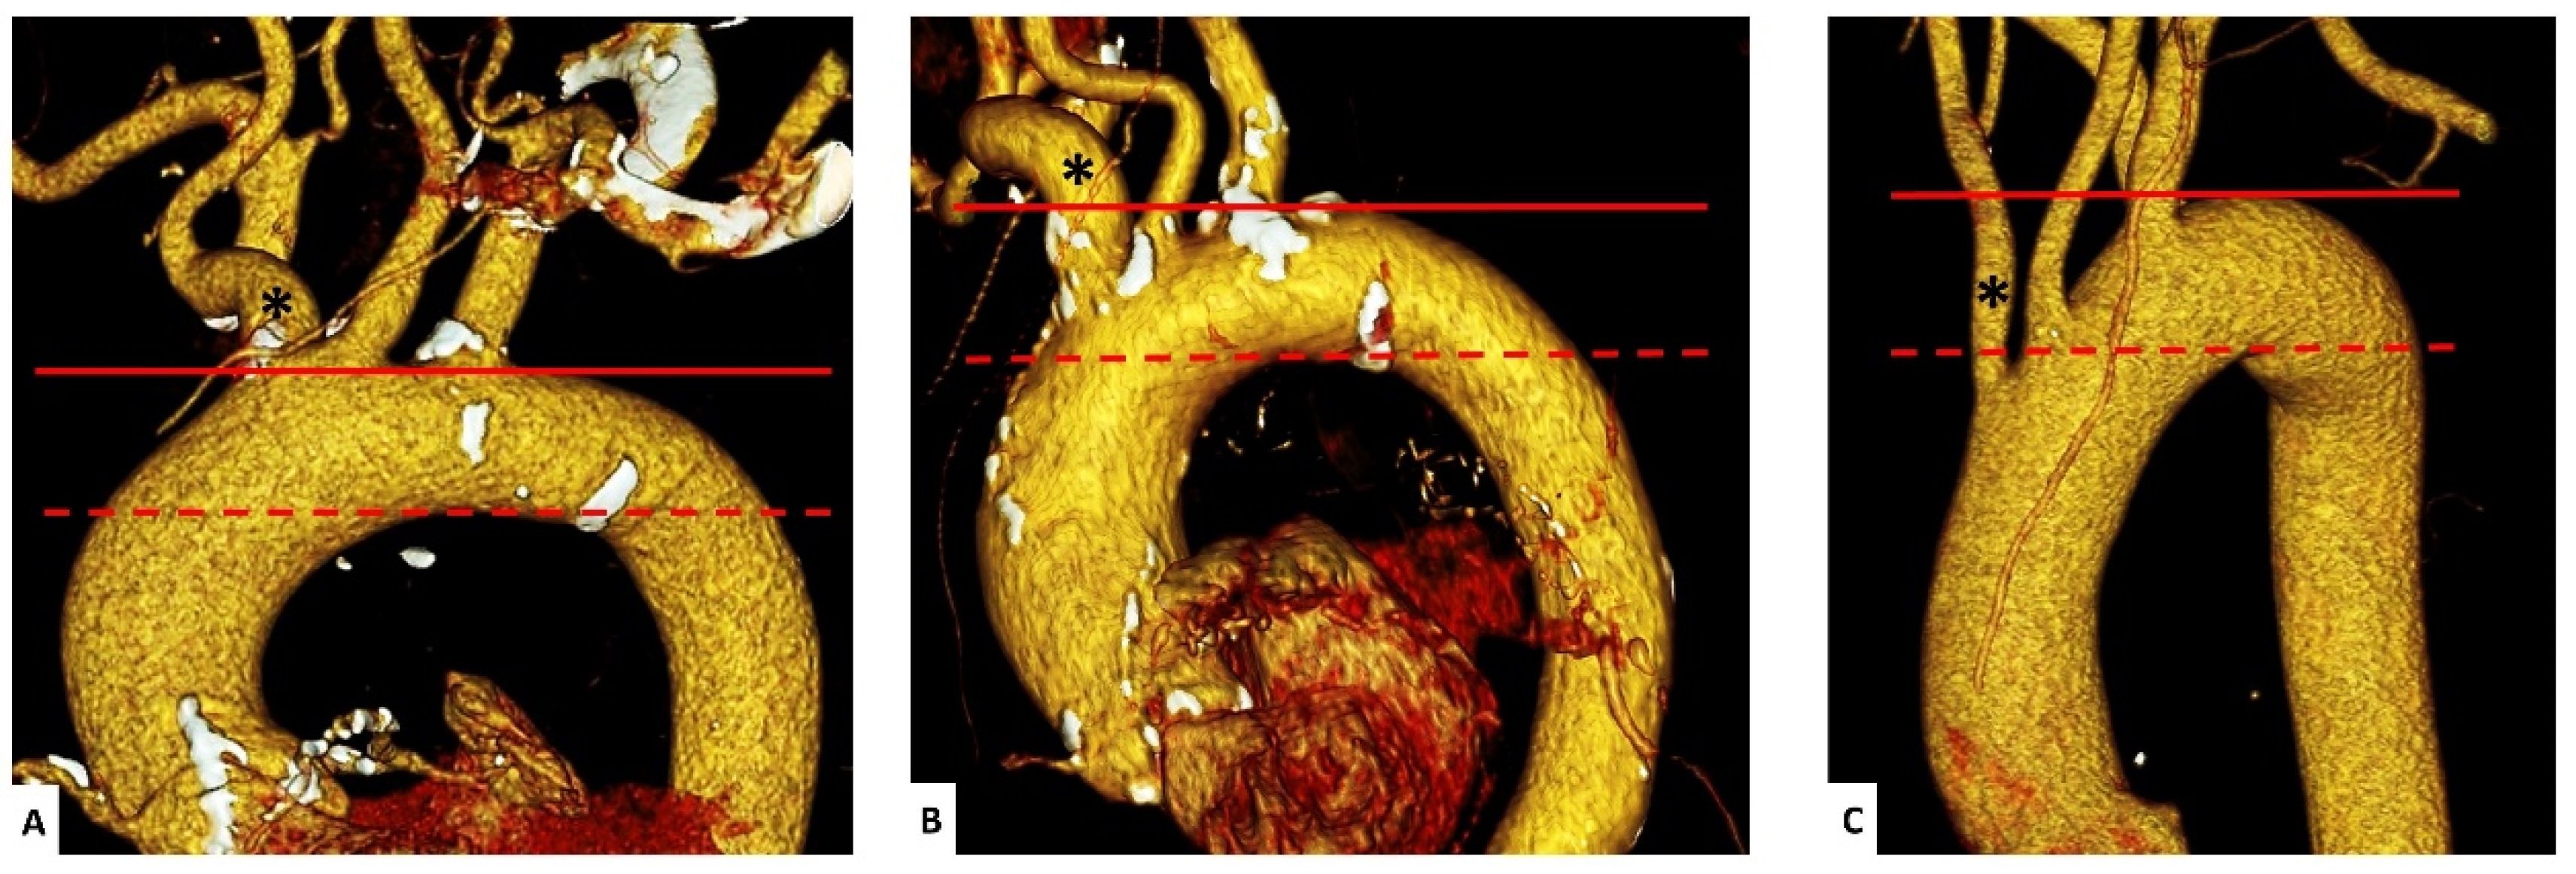

2.4. Assessment of Aortic Geometry